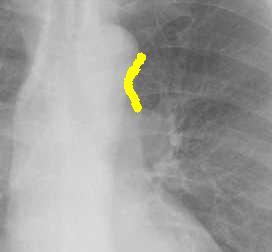

こちらを見て下さい。

わかりにくいかもしれませんが、このあたり。

気管が追いにくい、無くなっているようにも見えます。

気管狭窄ですね。こういう所見もレントゲンで捉えることができるのです。